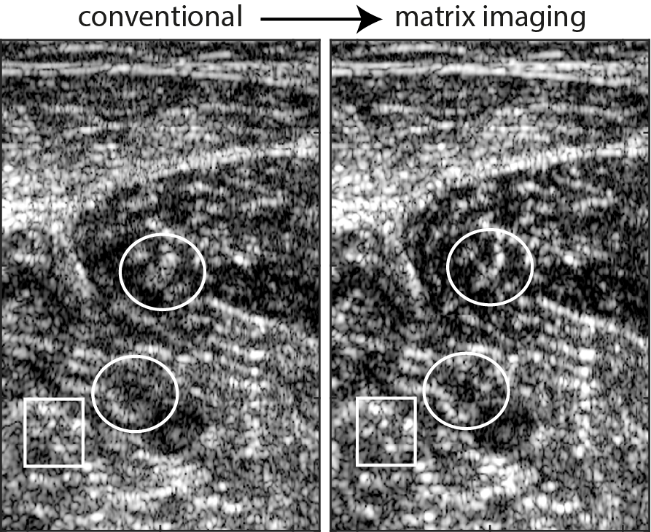

Conventional and matrix ultrasound images of a volunteer’s calf. Matrix correction of aberrations reveals structures that were previously invisible or had poor resolution in a conventional ultrasound (especially in the areas inside the white lines)

© Walter et al./PNAS